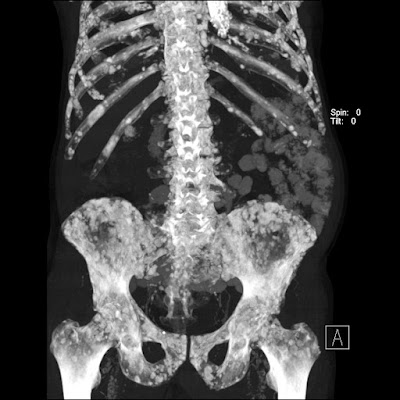

- Diffuse skeletal

- Oncohaematology